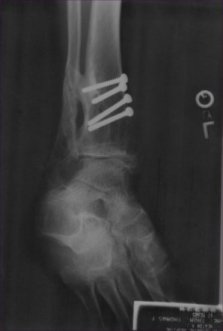

X-Ray Taken On April 22nd 2004

Leg Fracture Date: May 27, 1996

Fully Exposed Multiple Compound Fracture Left Leg